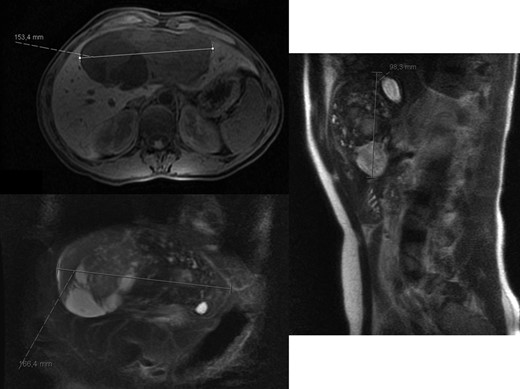

At 16 months, follow-up, local recurrence was identified on CT scan, showing an expansive heterogeneous lesion, below the stomach, with 7.4 cm of maximum diameter, showing no cleavage plan with the stomach (Fig. 4).

AP-CT – expansive heterogeneous lesion, with 7.4 cm, showing no cleavage plan with the stomach.

After 11 months of follow-up, the patient was admitted to the emergency room due to asthenia, nausea, vomiting and jaundice. CT scan reveal hepatic mass with 15.2 × 13.5 × 8.8 cm (Fig. 5) causing obstructive jaundice by compression of hepatic hilum.